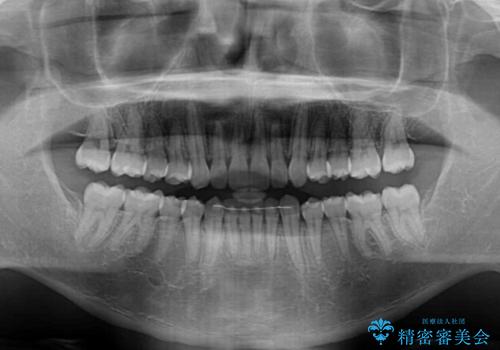

- 上下前歯のデコボコを気にして来院された患者様です。

インビザラインによる上下歯列の側方拡大と後方移動、IPR(歯と歯の間を削る)にるスペースの獲得により歯列を整えることとしました。

左上の小臼歯は捻転が強く、あえて180逆向きの状態で終了させる治療計画としました。

ご自宅と職場がともに遠方であったため、治療期間は長くなりましたが、患者様も我々も期待して以上に口元の突出感を改善することができました。